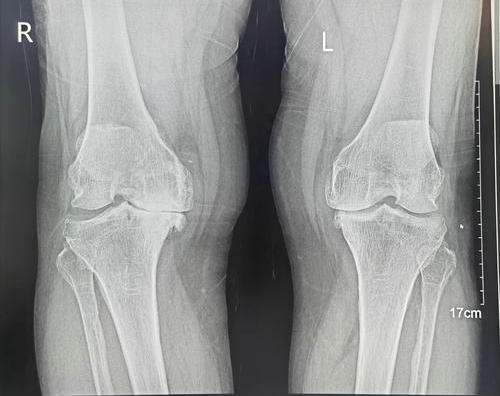

三、膝关节骨关节炎的诊断

诊断膝关节骨关节炎主要依据患者的临床表现、体格检查和影像学检查。X线检查是首选方法,可以显示关节间隙变窄、骨质增生等改变。必要时可进行CT、MRI等进一步检查,以明确退变部位和程度。此外,抽血化验可辅助诊断,如检查风湿系列、血沉等指标。